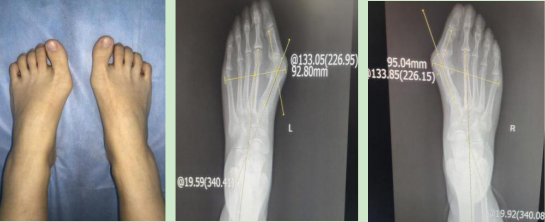

3.女性,24岁,微创踇外翻术后对比图

术前:左足HVA=46.95°,IMA = 19.59°右足HVA=46.15°,IMA = 19.92°

术后:左足HVA=7.59°,IMA = 6.86°右足HVA=13.92°,IMA = 10.05°